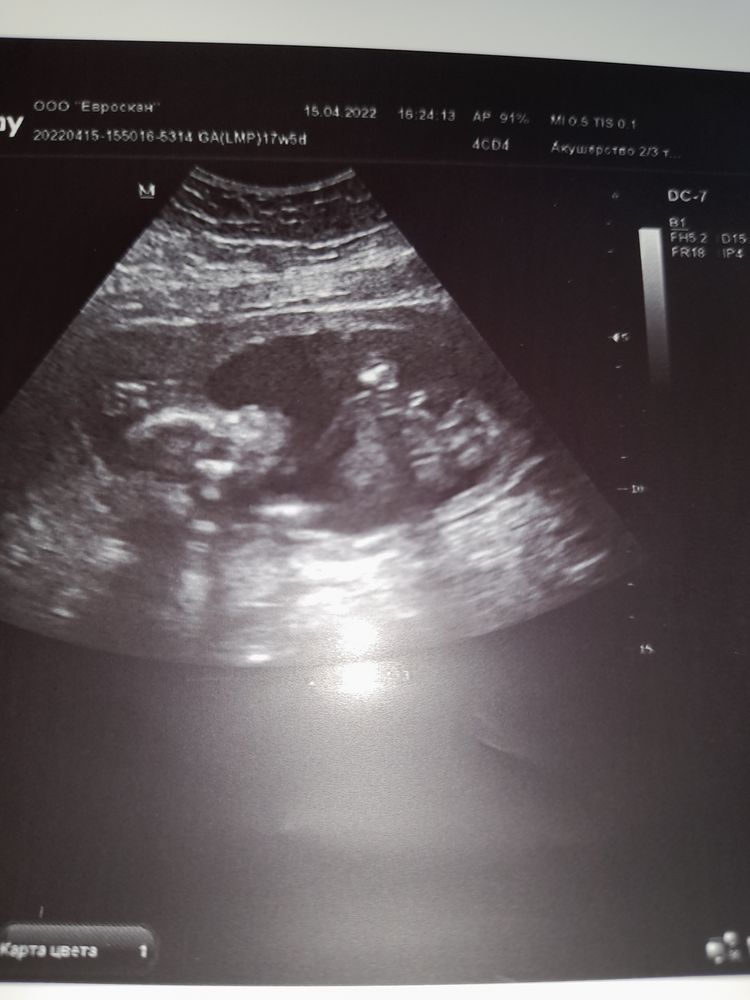

17+5 недель счастья🙏🥰😊

Сходила на узи плановое к своей Г. Идем в срок🙏 цервик.канал=45мм,плацента выше внутр.зева на 7см😊в общем ПАчиться нам можно🤭🤭🤭

Ну и конечно,у нас 100% подтвердили доченьку💃💃💃💕💕💕Малышка сейчас лежит ножками вниз,врач сказала,что может пинать мочевой🤔я и думаю,часто бегаю в тубзик,особенно ночью🤭

Всем планюшам желаю увидеть свои заветные //🙏 ну и немного нашей дамочки🥰